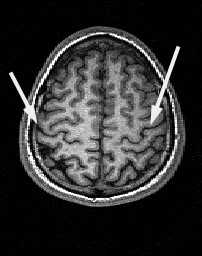

Центральная борозда (sulc.centralis) лучше видна в сагиттальной плоскости. Она расположена по середине между параллельными ей прецентральной и постцентральной бороздами. Существует много вариантов строения и хода борозды. Обычно она имеет значительную протяжённость и идёт в передне-нижнем направлении от межполушарной щели к Сильвиевой щели, которой достигает не всегда. Нижний конец борозды, либо продолжается в основном её направлении, либо загибается назад. Центральная борозда может прерывается по ходу. В поперечной плоскости на верхних срезах борозда имеет наибольшую протяжённость, доходя почти до межполушарной щели. Чем ниже срез, тем короче на нём центральная борозда. На уровне боковых желудочков она едва прослеживается . Центральная борозда разграничивает лобную и теменную доли .

МРТ головного мозга. Аксиальный срез. Центральная борозда (стрелки).